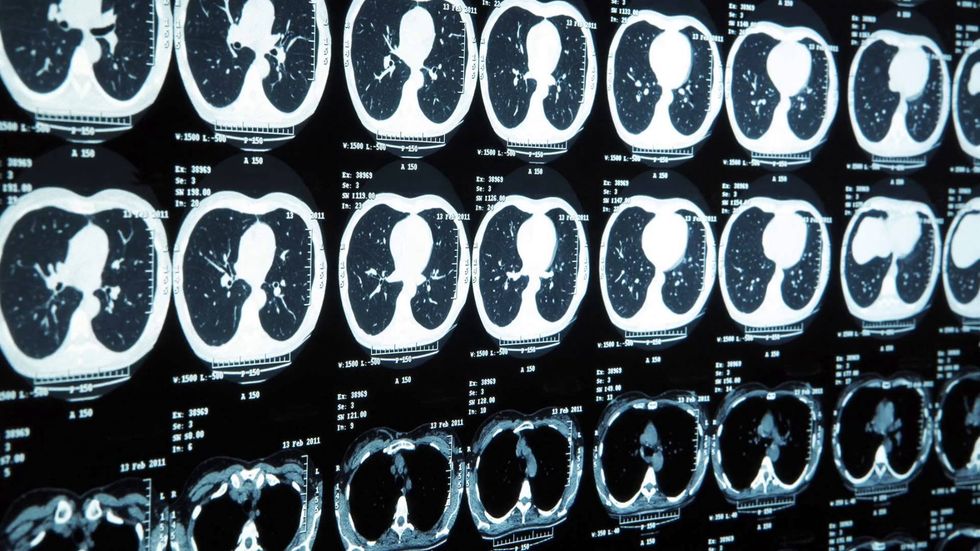

Let's face it. The future of the world's healthcare will be mostly run by robots. Your surgeries will be robotic. Maybe even nurses and doctors could be partially replaced with robots. Already today, biomedical engineering exists in MRIs and CAT scans and medical devices and genetic engineering and prosthetics. Right now, the field looks like this:

The large field of biomedical engineering includes the smaller fields of genetic engineering, tissue engineering, prosthetics, medical imaging, bioinformatics and many other fields, especially medical-related engineerings. This field has so much potential, and I think the world will forever change once new discoveries are made. Even now, potentially revolutionary research is being performed, like growing body organs in labs. Surgery could be perfected with robots, in which some are already used today, like the da Vinci machines. Here is a photo: